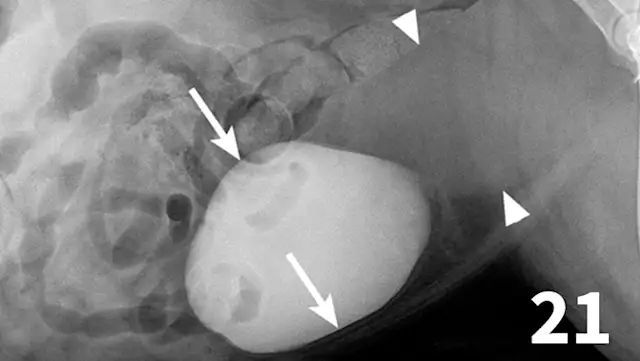

Positive-contrast cystography is useful when evaluation of urinary bladder location or integrity is questioned (Figures 21 and 22).

Double-contrast cystography can be an excellent tool to evaluate bladder wall thickness and any irregularities of the bladder mucosal surface and to rule out the presence of radiolucent cystouroliths (Figure 20). Although double-contrast cystography is more invasive because of the need for urethral catheterization, artifactual bladder wall thickening is usually not an issue because the degree of bladder distention can be controlled.